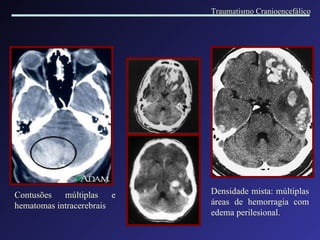

Contusões múltiplas e hematomas intracerebrais Densidade mista: múltiplas áreas de hemorragia com edema perilesional. Traumatismo Cranioencefálico

Hematoma intracerebral  Contusão hemorrágica multifocal Múltiplos pequenos focos hemorrágicos localizados em torno de vasos sanguíneos, no espaço de Virchow- Robin. Traumatismo Cranioencefálico